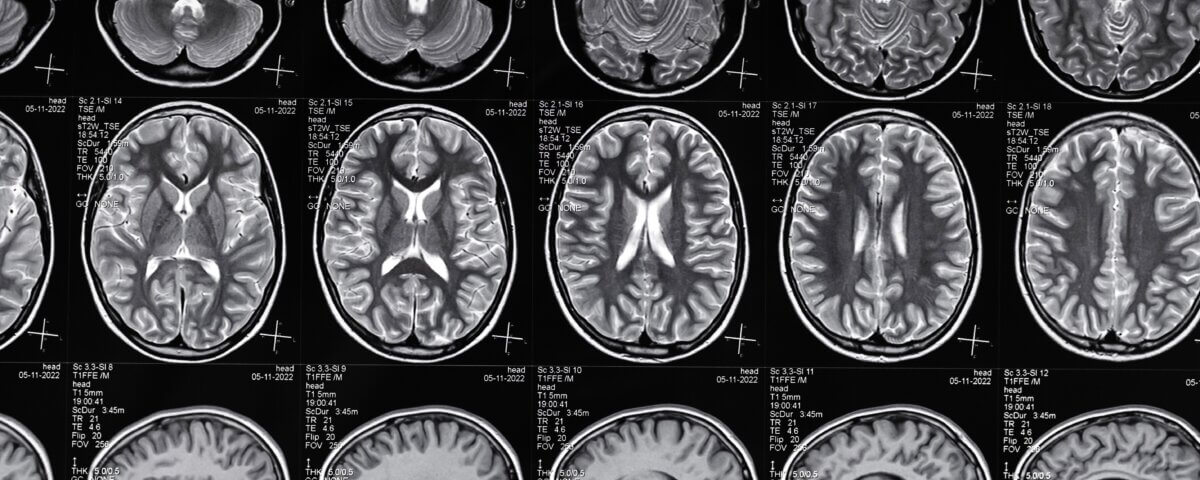

Every year many Americans are treated for traumatic brain injuries (TBIs), and thousands die from TBI-related complications. These injuries often lead to long-lasting or permanent disabilities and generate significant emotional, medical, and financial burdens for victims and their families.

Disclaimer: The material provided in these blogs is for general informational purposes only and should not be considered legal advice. Reading these posts does not create, and is not intended to create, an attorney-client relationship with Hillstone Law. Our intent is to share knowledge, raise awareness, and provide helpful resources to the public; however, Hillstone Law makes no warranties or guarantees about the accuracy, completeness, or reliability of the information provided, and expressly disclaims liability for any actions taken in reliance on it. The photos used in these posts are for illustrative purposes only and do not depict actual clients, individuals, or incidents unless expressly stated. If you or a loved one has been injured in an accident, please contact Hillstone Law at (855) 691-1691. Our attorneys are available to answer your legal questions and help you understand your rights.